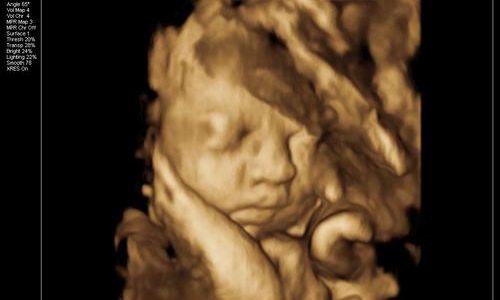

朋友28周的时候叫我陪着去体检,给宝宝照下四维彩照,看看胎儿生长发育过程中有没有变畸形。

因为宝宝在子宫内发育的非常好,活蹦乱跳的。半个小时,朋友拿着四维彩照的照片一言难尽。

这也太丑了吧!朋友说自己和老公的长相都不差,为什么生育的孩子确实塌鼻梁、大鼻孔、厚嘴唇呢?

那山根宽的像座独木桥,整个一阿凡达!欲哭无泪的朋友觉得打击太大,连着好几天都沉浸在悲伤中不能自拔。

真的是这样吗?专家解答说,其实四维彩照出来的成像与宝宝出生后的模样会有一定出入,以下三张图片告诉你。

一般孕妇在正常情况下都是在28周的样子去拍四维,可是你们要知道这个时期的宝宝还没有完全发育成熟。拿苹果举例,从青涩到成熟得经历一段时间,而28周的胎儿就相当于七分熟的苹果。

胎儿的面部脂肪还没有完全堆积,因此从四维看到的脸蛋来说是比较丑的,类似于外星人。头部和身体的占比例大概是2:1,以成年人的视觉来看可不是怪异么。

再者,孕妇拍摄四维的目的,便是排除胎儿面部是否畸形。所以会根据声波成像技术来填充图像,再将口、鼻、眼等细节放大。

但是小宝宝的口耳鼻实在太细节,声波反弹较弱,因此连接到电脑上后会另外填充成像。毕竟四维彩照和我们平时拍照的像素不一样,它是由彩超探头采集到的数据以此合成一个大致的影像。

那么打印出来后自然模糊,边缘不清晰,导致小宝宝的五官和肢体看起来扭曲变形。一定程度上*化丑**了宝宝,让新手爸妈们怀疑人生。

所以,在探头勘测超声波影像时,胎儿在动。加上胎儿整个是泡在羊水里面,左动一下,右动一下,拍摄出来的成像难免会失真。

综上所述,四维彩照出来的胎儿成像,并不会是宝宝实际出生的样子。就和我们去一个餐厅吃饭一样,实物与图片不符。